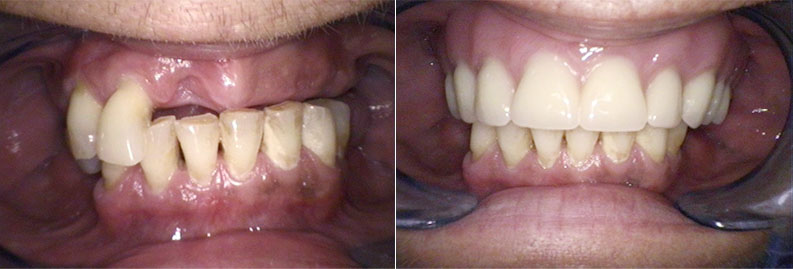

Prosthodontics

Prosthodontics focuses on the restoration and replacement of missing teeth. We offer both removable prostheses, such as partial or full dentures, and fixed prostheses, including crowns and bridges. These restorations are custom-made to blend seamlessly with your natural teeth, restoring the function, appearance, and confidence that come with a complete smile.